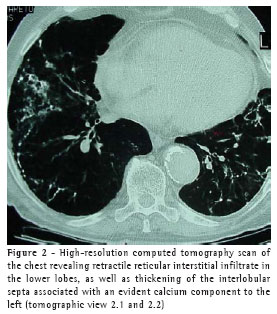

A chest X-ray (Figure 1) showed retractile interstitial infiltrate in the lung bases, rectification of the hemidiaphragm with ill-defined borders, diffuse increase in pulmonary transparency in the upper and middle lobes, and enlarged cardiac image, as well as an aorta affected by ectasia and atheromatosis.